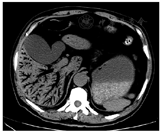

入院查体:体温36.5℃,血压131/70 mmHg,脉搏105次/min,呼吸25次/min。腹部膨隆,叩诊鼓音区扩大,听诊1 min未闻及肠鸣音,全腹轻度压痛。疼痛以右上腹为著,疼痛强度为8/10[视觉模拟评分(VAS)]。实验室检查:白细胞9.49×109/L,中性粒细胞74.3%,血红蛋白138 g/L;C反应蛋白22.3 mg/L;丙氨酸转氨酶9.1 U/L,天冬氨酸转氨酶6.4 U/L,总胆红素8.4 μmol/L,直接胆红素4.2 μmol/L,尿素氮35.18 mmol/L,空腹血糖6.53 mmol/L,血肌酐1 251.9 μmol/L,血钾5.09 mmol/L,血淀粉酶194 U/L;大便潜血阳性。腹部平片显示小肠和结肠弥漫性扩张;腹部CT显示肠腔扩张和广泛的肝门静脉积气(hepatic portal venous gas,HPVG)(图1)。

注:肝门静脉及其各分支(延伸至肝包膜下2 cm)中存在大量气体影